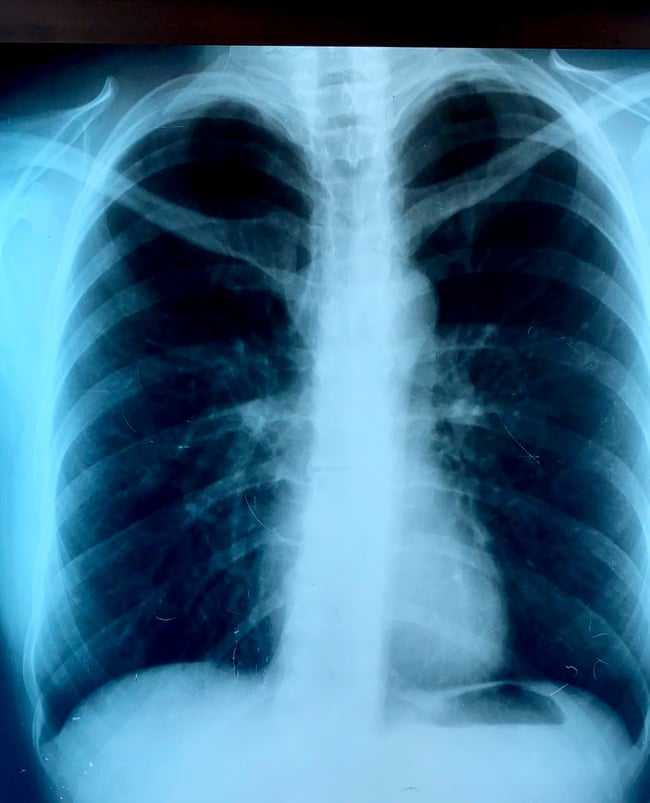

Dijagnoza se postavlja na osnovu anamneze gde su presudni podaci o pušenju ili velikoj izloženosti aerozagađenju na radnom mestu i životnoj sredini. Za postavljanje sigurne dijagnoze i utvrđivanje stepena HOBP koriste se spirometrijski test, analize krvi, rendgenski snimci i skener – CT pluća.